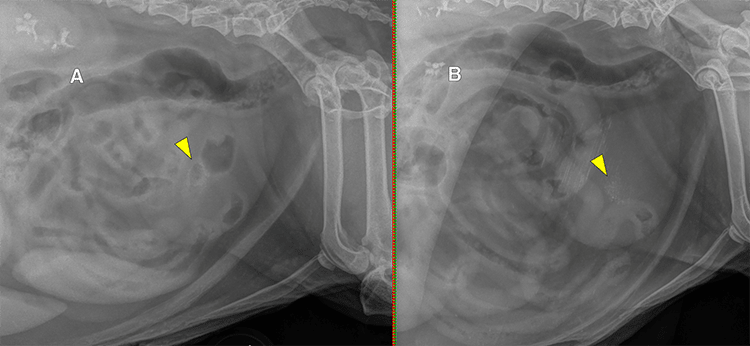

Bladder calculi can range from amorphous sediment to tiny sand-like foci to variably spiculated or smooth stones, which occur singly or in clusters. Care should be taken not to over-interpret the presence of mineral calculi in the urinary bladder if there are also intestinal segments (especially the colon) superimposed on the bladder. A useful technique for isolating the bladder during a lateral radiographic exposure is to apply compression over the bladder using a radiolucent wood or plastic paddle (the hand holding the paddle should be in a leaded glove, of course). The compression will push intestinal segments away from the bladder, and the mineral calculi should be visible through the radiolucent paddle. (Figure 3)

Figure 3: Lateral radiographs without (A) and with (B) lateral compression of the bladder with a wooden paddle in a patient with granular mineral cystic calculi (yellow arrowheads). While the mineral calculi are visible at the center of the bladder without compression, there are multiple intestinal segments also superimposed on the bladder. Paddle compression displaces the intestinal segments away from the bladder, allowing for definitive identification of calculi within the bladder (unfortunately, the paddle we use at Angell is somewhat old and dirty, resulting in some additional mineral opaque streaking).